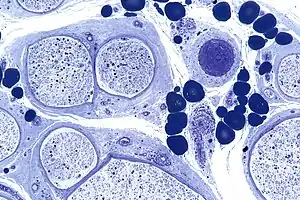

Micrograph showing a vasculitic peripheral neuropathy; plastic embedded; Toluidine blue stain